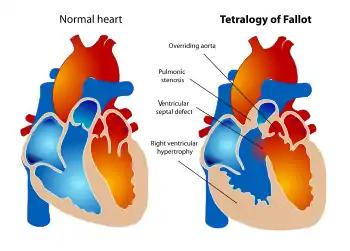

| Diagram of a healthy heart and one with tetralogy of Fallot | |

Tetralogy of Fallot (TOF), formerly known as Steno-Fallot tetralogy,[9] is a congenital heart defect characterized by four specific cardiac defects.[4] Classically, the four defects are:[4]

- pulmonary stenosis, which is narrowing of the exit from the right ventricle;

- a ventricular septal defect, which is a hole allowing blood to flow between the two ventricles;

- right ventricular hypertrophy, which is thickening of the right ventricular muscle; and

- an overriding aorta, which is where the aorta expands to allow blood from both ventricles to enter.

Four malformations

"Tetralogy" denotes four parts, here implying the syndrome's four anatomic defects.[2] This is not to be confused with the similarly named teratology, a field of medicine concerned with abnormal development and congenital malformations (including tetralogy of Fallot). Below are the four heart malformations that present together in tetralogy of Fallot:

| Condition | Description |

|---|---|

| Pulmonary Infundibular Stenosis | A narrowing of the right ventricular outflow tract. It can occur at the pulmonary valve (valvular stenosis) or just below the pulmonary valve (infundibular stenosis).[4] Infundibular pulmonic stenosis is mostly caused by the overgrowth of the heart muscle wall (hypertrophy of the septoparietal trabeculae),[41] however, the events leading to the formation of the overriding aorta are also believed to be a cause. The pulmonic stenosis is the major cause of the malformations, with the other associated malformations acting as compensatory mechanisms to the pulmonic stenosis.[42] The degree of stenosis varies between individuals with TOF and is the primary determinant of symptoms and severity. This malformation is infrequently described as sub-pulmonary stenosis or subpulmonary obstruction.[43] |

| Overriding aorta | An aortic valve with biventricular connection, that is, it is situated above the ventricular septal defect and connected to both the right and the left ventricle. The degree to which the aorta is attached to the right ventricle is referred to as its degree of "override." The aortic root can be displaced toward the front (anteriorly) or directly above the septal defect, but it is always abnormally located to the right of the root of the pulmonary artery. The degree of override is extremely variable, with 5-95% of the valve being connected to the right ventricle.[41] |

| Ventricular septal defect (VSD) | A hole between the two bottom chambers (ventricles) of the heart. The defect is centered around the most superior aspect of the ventricular septum (the outlet septum), and in the majority of cases is single and large. In some cases, thickening of the septum (septal hypertrophy) can narrow the margins of the defect.[41] |

| Right ventricular hypertrophy | The right ventricle is more muscular than normal, causing a characteristic boot-shaped (coeur-en-sabot) appearance as seen by chest X-ray. Due to the misarrangement of the external ventricular septum, the right ventricular wall increases in size to deal with the increased obstruction to the right outflow tract. This feature is now generally agreed to be a secondary anomaly, as the level of hypertrophy tends to increase with age.[44] |